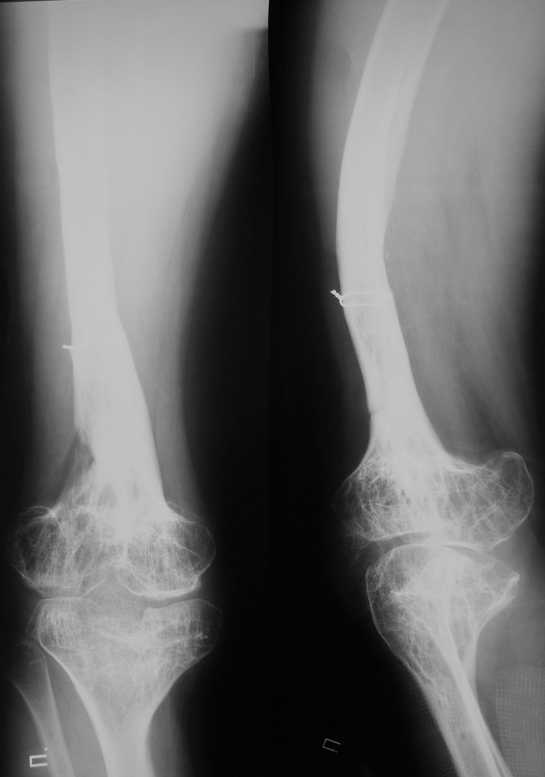

Фиброзная дисплазия бедра, укорочение 12 см.

Несколько лет нами наблюдается пациент с фиброзной дисплазией бедра (сейчас ему 18 лет).

В анамнезе 2 операции: 1.корригирующая остеотомия бедра с резекцией и аутопластикой на месте псевдоартроза бедра в н/3. 2.кортикотомия, дистракционный остеосинтез бедра в аппарате. Последний аппарат находился на больном 1г 3мес и еще 1 год ношения ортеза в связи с замедленной консолидацией.

Сейчас ортопед. укорочение конечности составляет 12 см (7 см-бедро и 5 см-голень)Движения в коленном суставе после удлинения 180-130.Удлинение бедра рикованно и грозит несращением и стойкой контрактурой колена.

Спасибо за ответы. Это рентгенограммы пациента до и после последнего удлинения бедра